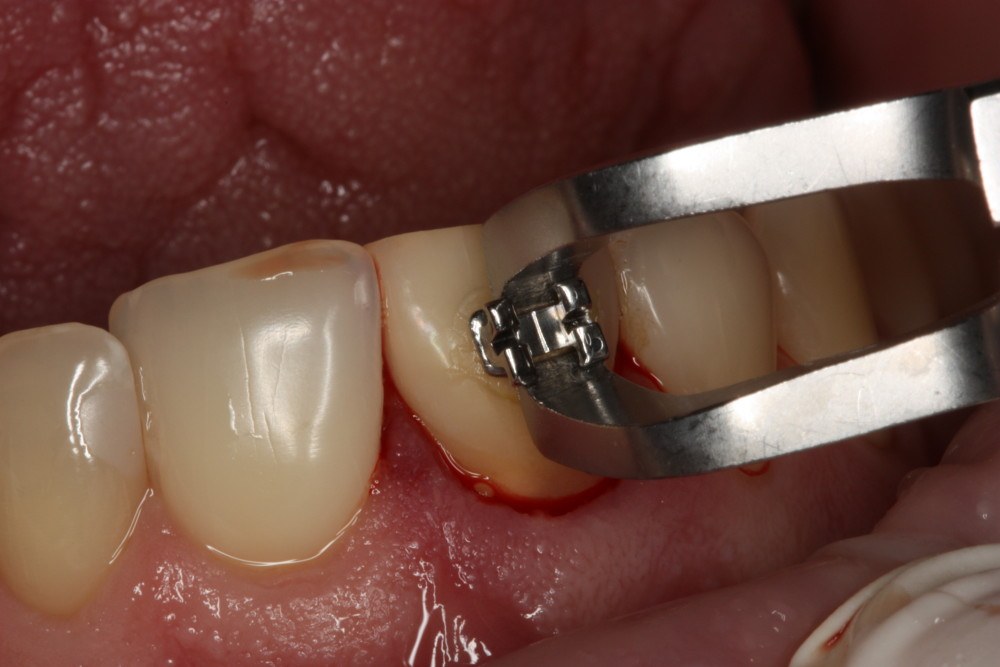

Przykład ekstruzji ortodontycznej za pomocą płytki termoformowalnej i zameczka ortodontycznego: